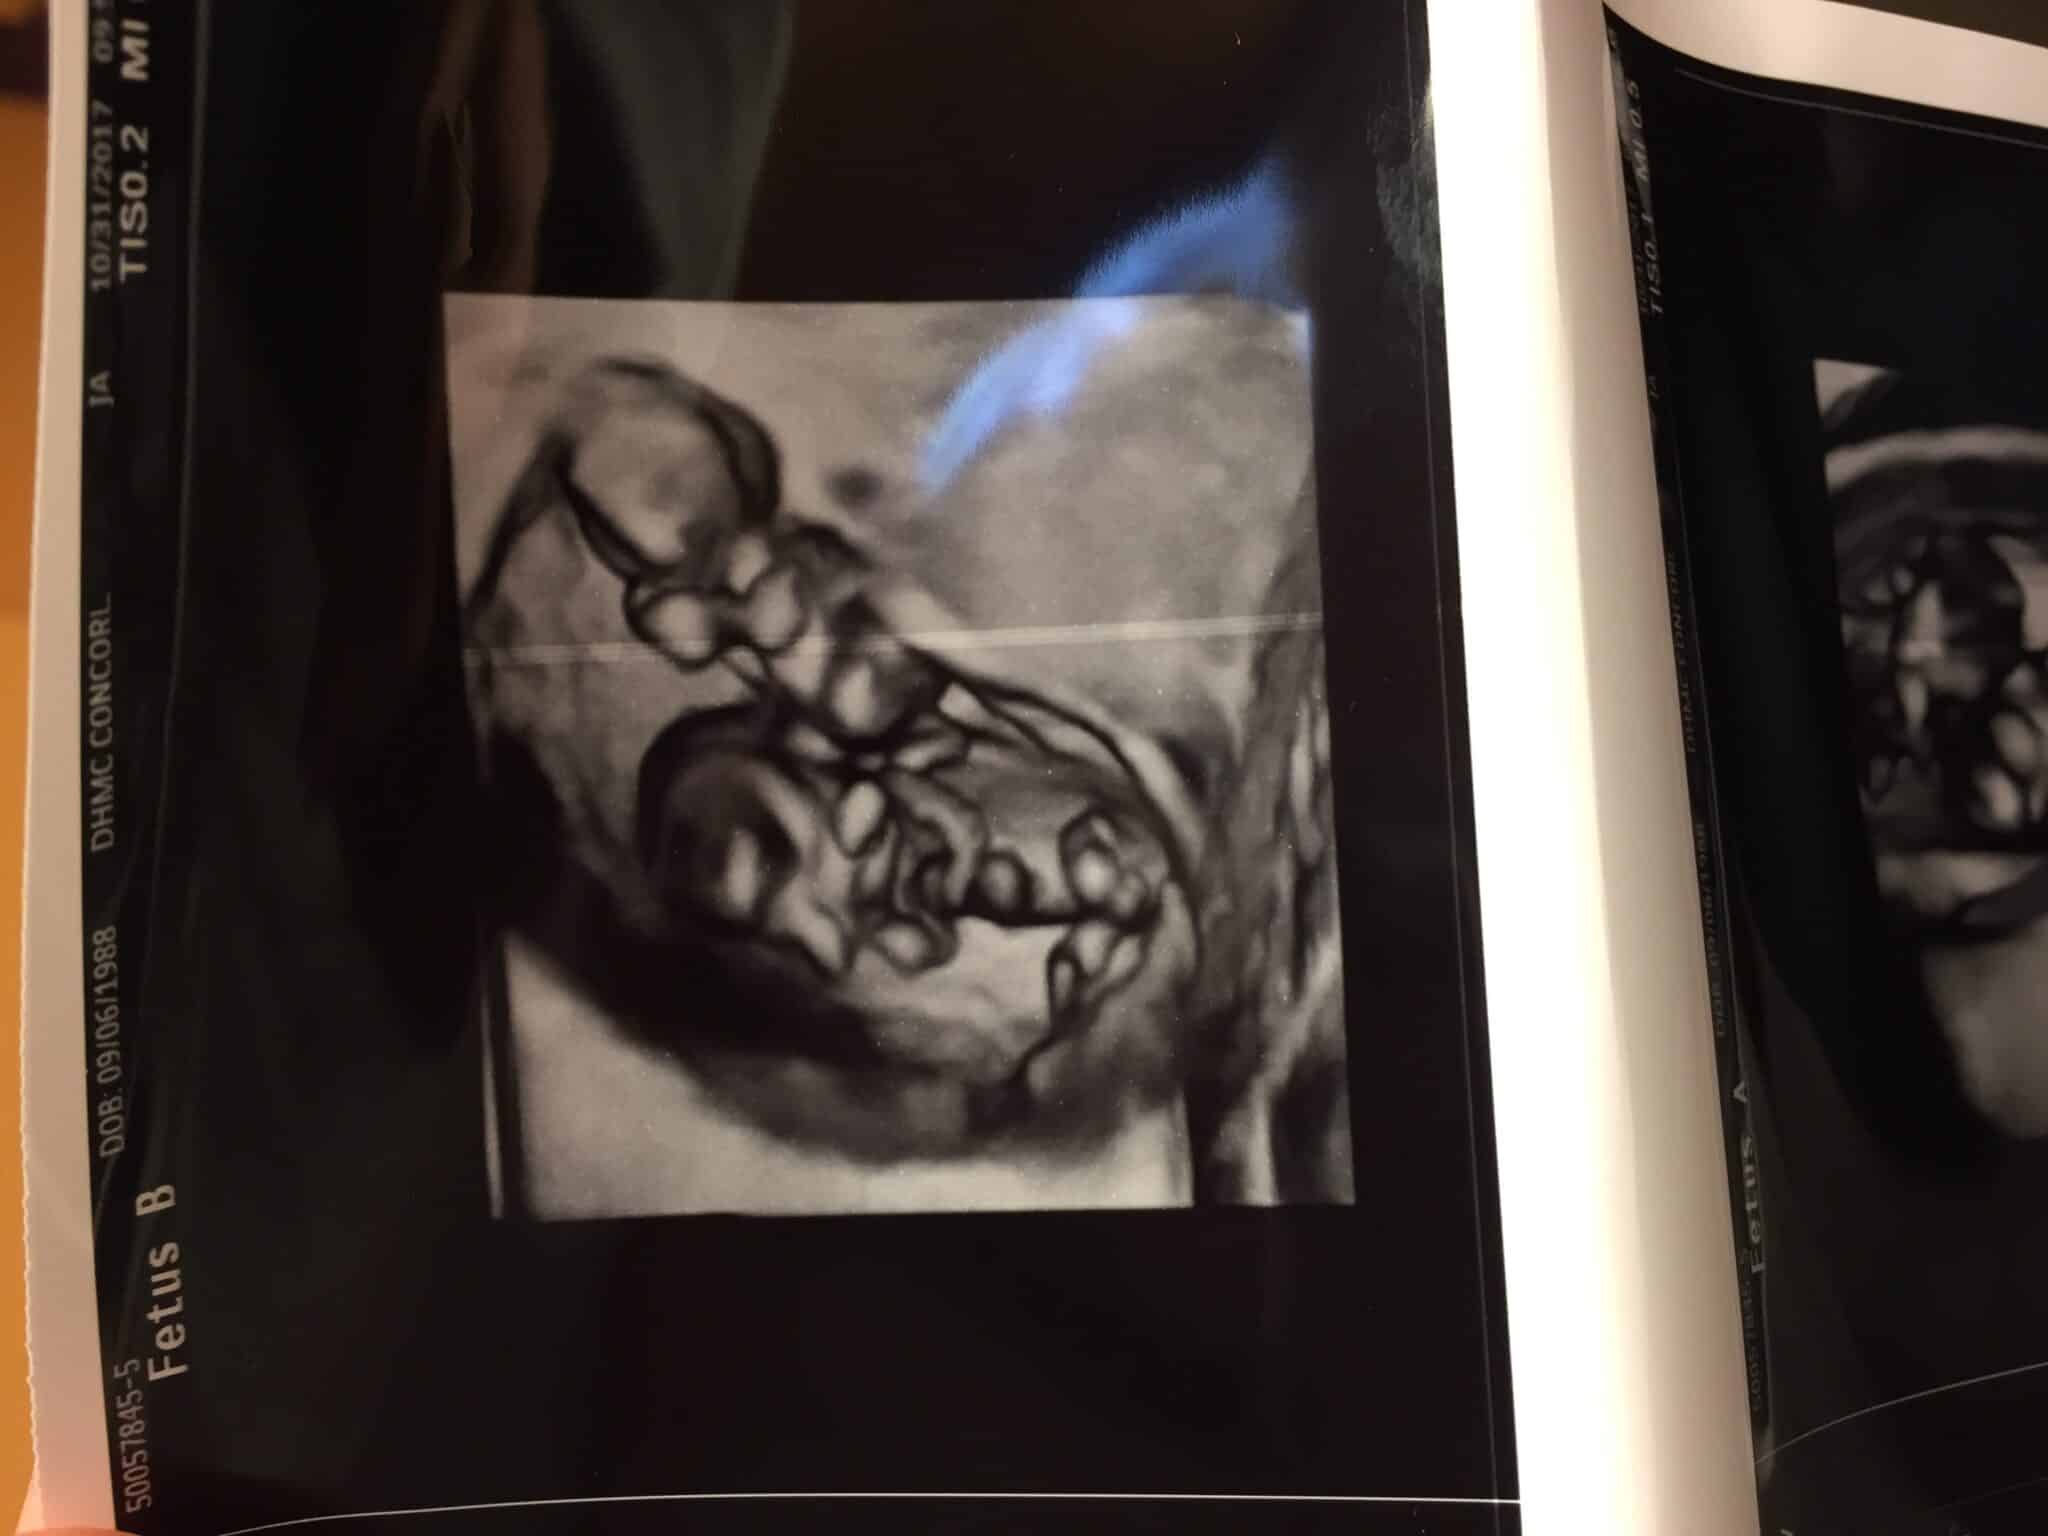

Ultrasound Photos at 11 Weeks Pregnant With Twins